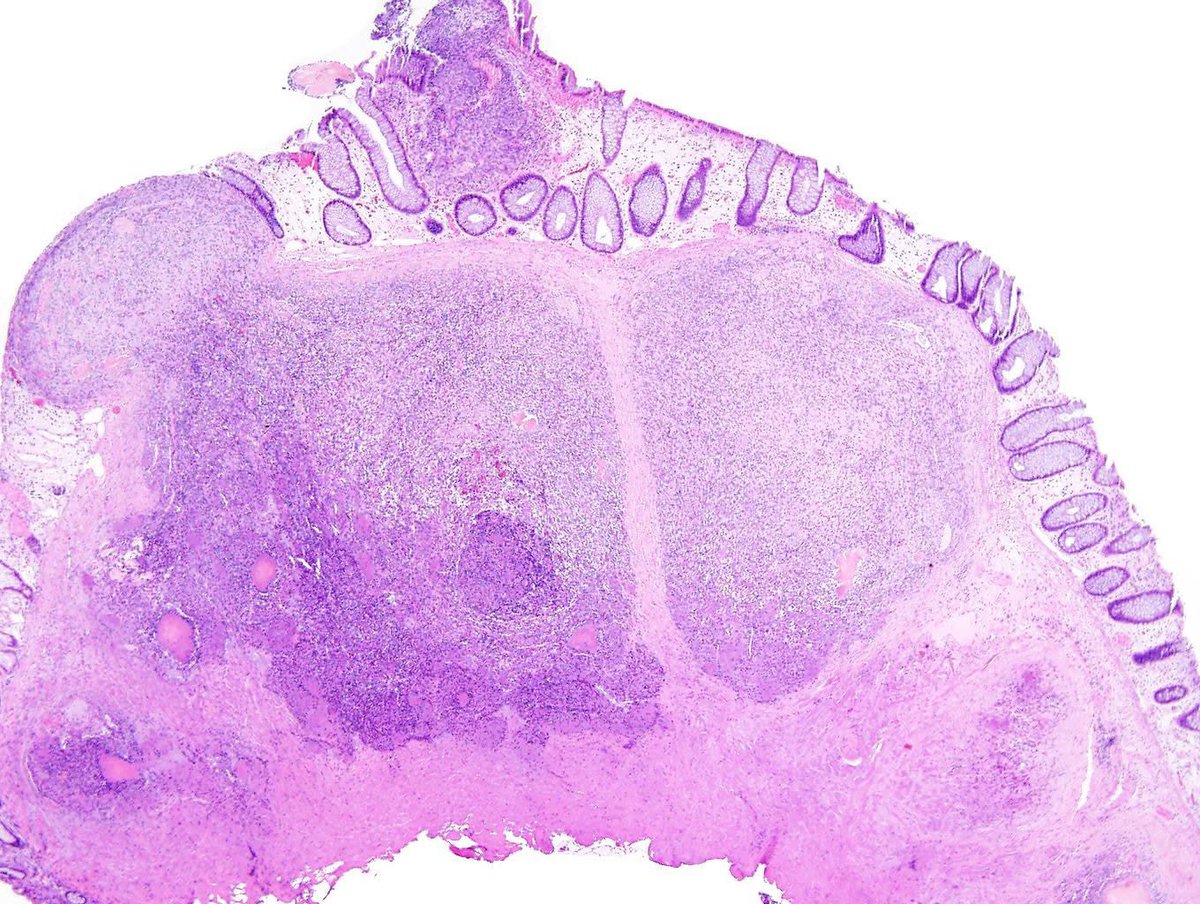

After a long Twitter hiatus because... life... I'm back to bring you this endometrial lesion in a 42 yo woman with abnormal uterine bleeding. Hysteroscopy showed an endometrial polyp in the lower uterine segment #GynePath #GynPath #PathTwitter